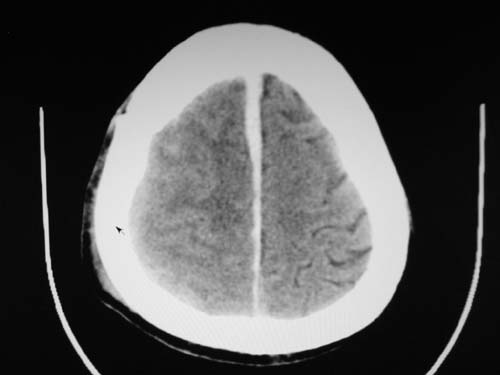

标题: CT17020:是硬膜下的吗?

脑中线内血肿,是硬膜下的吗?

脑中线内血肿——硬膜下血肿。

脑中线内血肿——硬膜下血肿。我们一般认为中线即可是硬膜下,也可是蛛网膜下腔的。边缘锐利,张力高的考虑硬膜下的,边缘模糊的,考虑下腔的。如果有老师有肯定的答案,麻烦下给我发个短信

支持镰旁硬膜下血肿,颅骨骨折,头皮损伤.

这个病人年龄不小吧,右侧脑沟不清,中线结构稍有左移,右侧额颞顶及右镰旁硬膜下血肿,另有蛛血,骨折。

外伤后引起的颅骨骨折、硬膜下血肿、皮下血肿,颅骨骨折引起的矢状窦破裂,形成大脑纵裂内血肿。